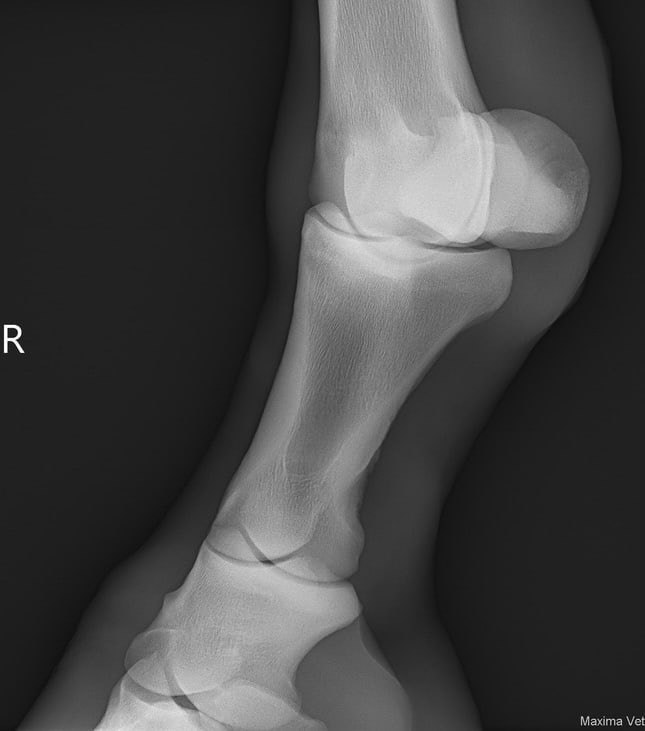

При МРТ-исследовании достаточно очевидны следующие изменения:

ЛЕВАЯ грудная конечность:

Переполнение и синовит копытного сустава, выраженное нарушение структуры

навикулярной кости.

ПРАВАЯ грудная конечность:

Переполнение и синовит копытного сустава.

Но наиболее интересным выглядит фрагментация дистального края навикулярной

кости.

ПРЕДВАРИТЕЛЬНЫЙ диагноз:

Остеоартроз копытных суставов правой и левой грудных конечностей. Навикулит.

Отрыв дистальной связки навикулярной кости с фрагментом навикулярной кости.

На МРТ-снимках достаточно хорошо видны изменения, которые никаким образом

не были видны при других методах исследования.

Поэтому лошадям со сложной хронической хромотой мы рекомендуем делать

МРТ, чтобы поставить точный диагноз и назначить более точное лечение, тем

самым вылечить лошадь и дать шанс на дальнейшую спортивную карьеру.